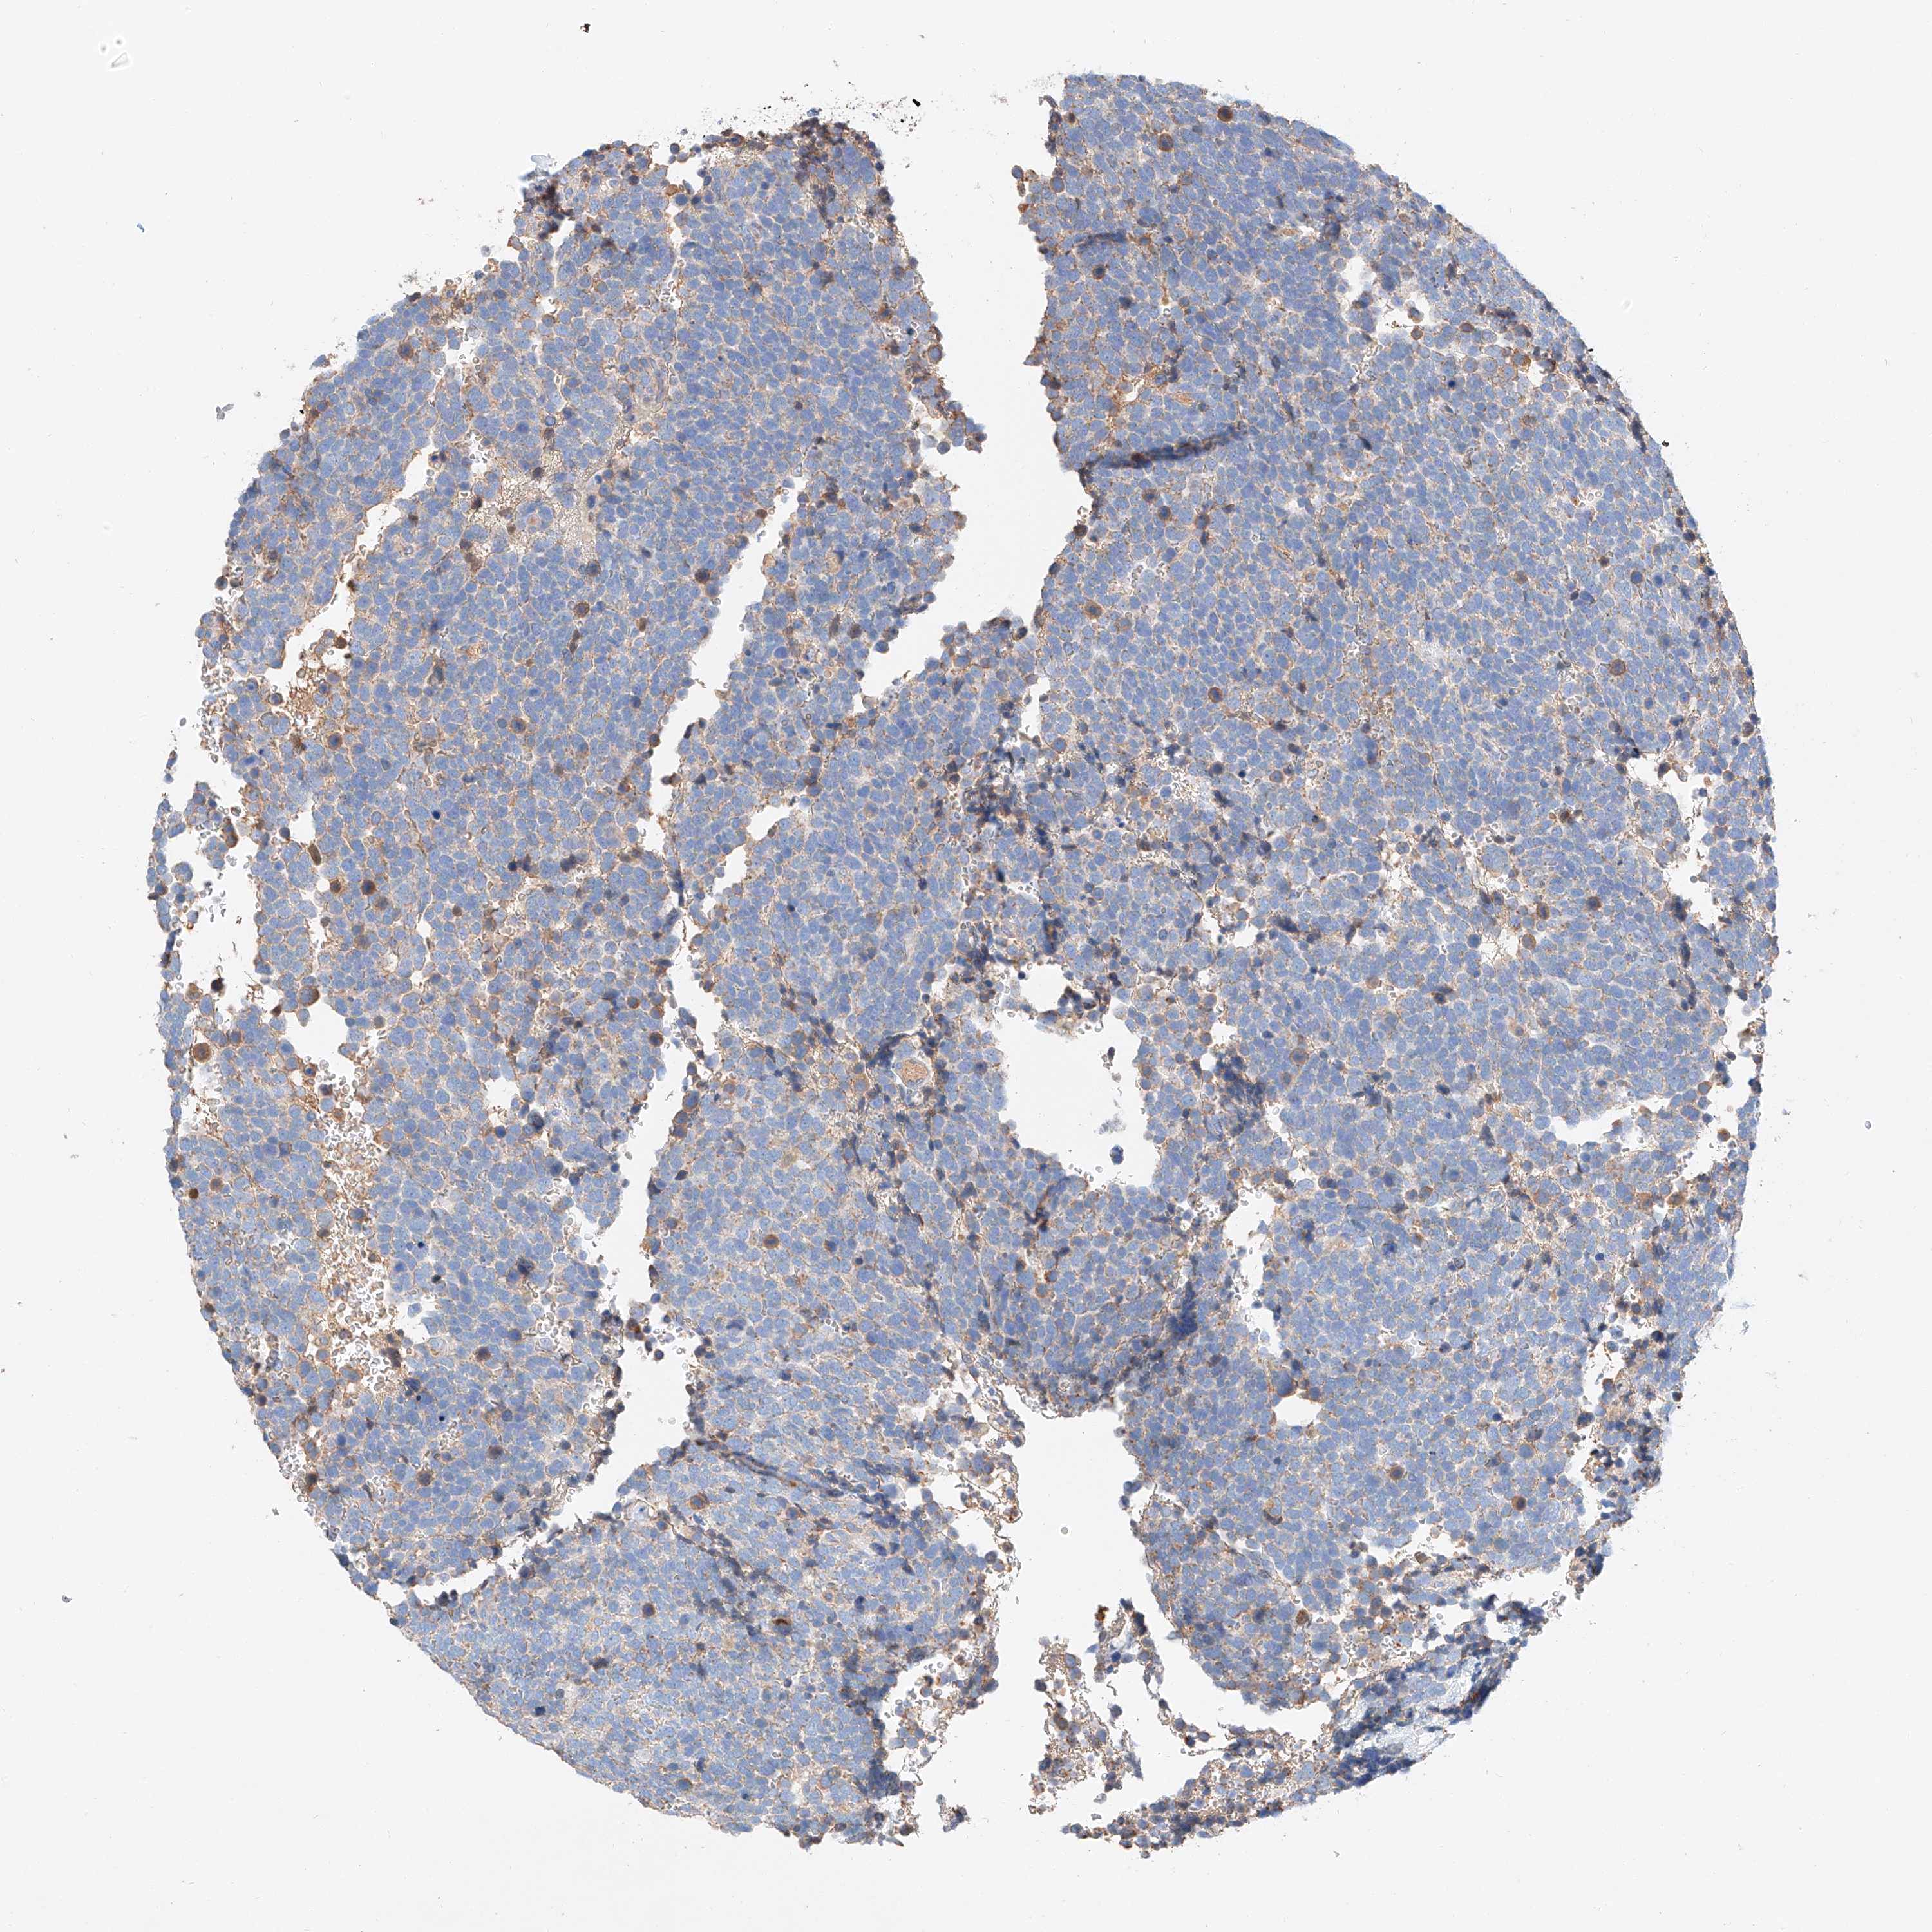

UROTHELIAL CANCER - Protein expressioni

A mouse-over function shows sample information and annotation data. Click on an image to view it in a full screen mode. Samples can be filtered based on level of antibody staining by selecting one or several of the following categories: high, medium, low and not detected. The assay and annotation is described here.

Note that samples used for immunohistochemistry by the Human Protein Atlas do not correspond to samples in the TCGA dataset.

Antibody stainingi

Antibody staining in the annotated cell types in the current human tissue is reported as not detected, low, medium, or high, based on conventional immunohistochemistry profiling in selected tissues. This score is based on the combination of the staining intensity and fraction of stained cells.

Each image is clickable and will lead to virtual microscopy that enables deeper exploration of all samples and also displays staining intensity scores, fraction scores and subcellular localization as well as patient and tissue information for each sample.

Antibody HPA030295

Antibody HPA054323

Urothelial carcinoma, Low grade

Urothelial carcinoma, High grade